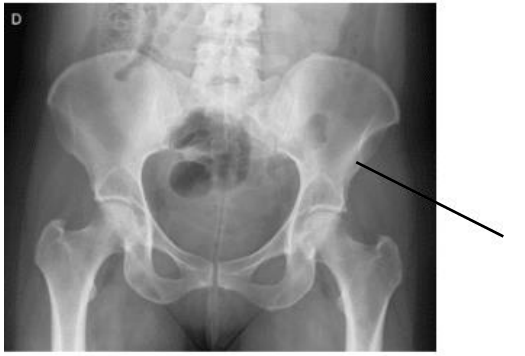

No exame abaixo podemos visualizar um detalhe anatômico ósseo denominado:

Fonte: https://anatomia-papel-e-caneta.com/posicionamento-radiologico-mmii-bacia-quadril/